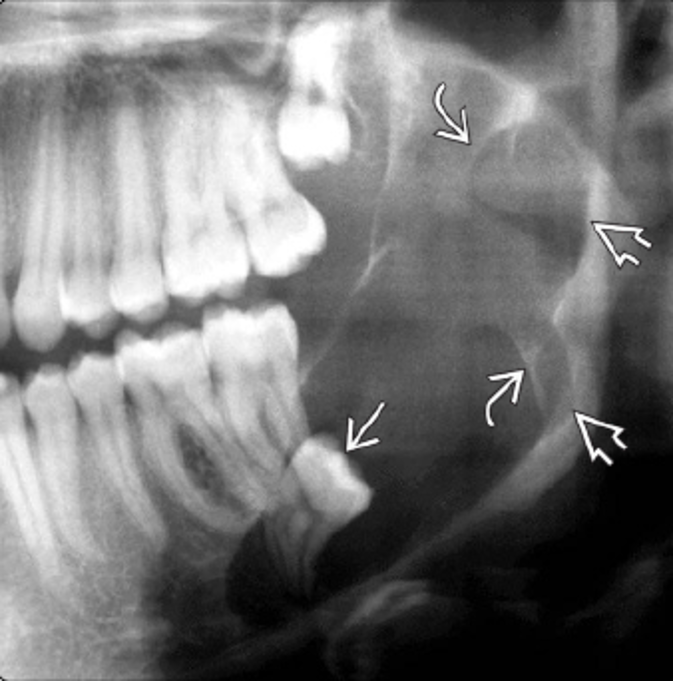

En estas imágenes te mostramos varios casos de la misma patología.

Participa describiendo la patología, dando diagnósticos diferenciales o cualquier comentario que sea útil.

Posterior a sus respuestas estaremos revelando los casos con su información en los comentarios.